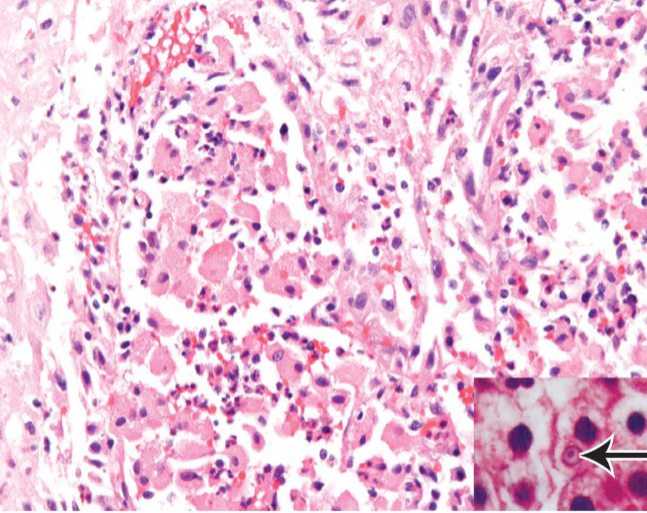

Malakoplakia

usually in context of chronic bacterial infection or immunosuppressed transplant patients

Path → sheets of macrophages with abundant granular cytoplasm (Phagolysosomes with bacterial fragments) & mineralized inclusions (Michaelis-Gutmann bodies)

Soft, yellowish plaques

concentrically layered Michaelis-Guttman bodies

Macrophages with abundant eosinophilic granular cytoplasm

Michaelis-Gutmann body

Michaelis-Gutmann bodies containing Iron & Calcium